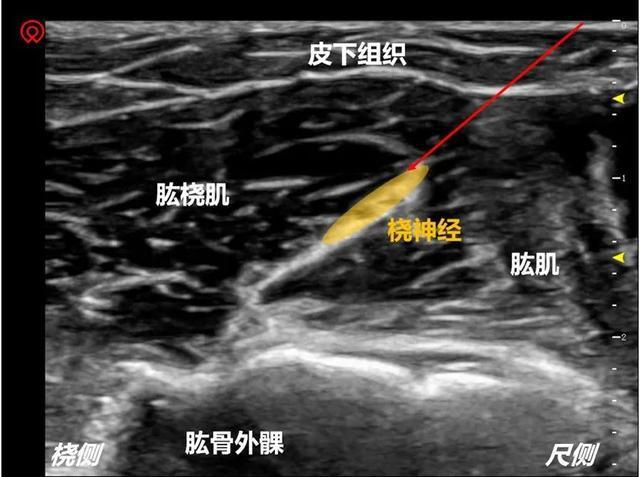

桡神经超声

桡神经超声,桡神经

瑞金专题超声引导下桡神经阻滞

桡神经

桡神经损伤